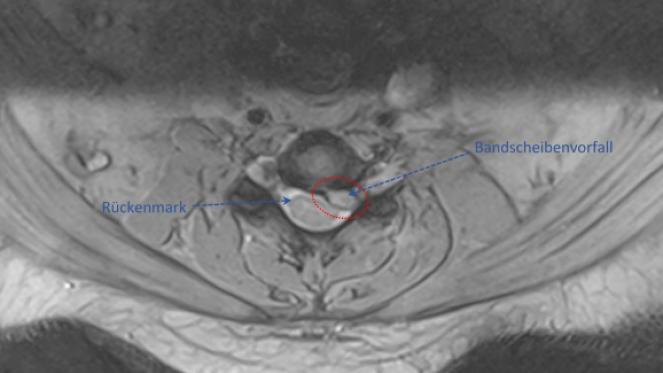

Bandscheibenvorfälle (NPP)

Bandscheiben sind flexible, faserknorpelige Verbindung, die als Stoßdämpfer zwischen den Wirbel dienen.

Mit zunehmendem Lebensalter kann es zu verschleißbedingten Rissen am äußeren Ring der Bandscheibe (Faserring) und zu einem Austritt des gallertartigen Kerns kommen. Dieser kann die benachbarten Nervenwurzeln oder das Rückenmark zusammendrücken und zu lokalen oder ausstrahlenden Schmerzen in den Armen und Beinen, ggf. auch mit Sensibilitätsstörungen und motorischen Ausfällen, führen.